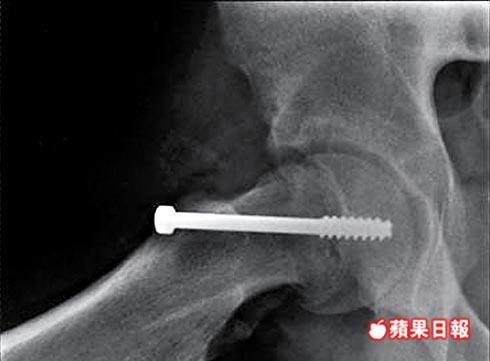

打石膏鑲螺絲固定骨頭

由於此病的早期症狀不明顯,患者在確診前往往已嘗試不同的治療,易令病情惡化。李閏海表示,患者可以石膏、螺絲等方法固定移位的骨頭,也可接受切骨手術,糾正骨頭方向。

李閏海強調,因患者正處於發育期,若未能及早發現移位,病情可在短時間內惡化,影響手術成效,故提醒青少年要保持正常體重,若出現以上症狀應盡快求診。